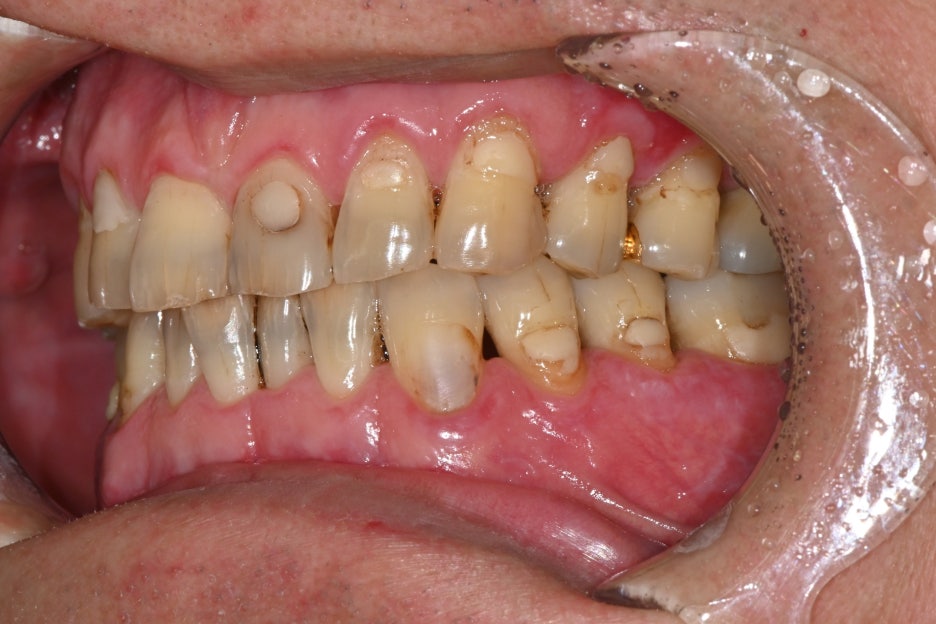

The patient visited with the chief complaint that “the lower left molar was extracted a long time ago, and lately I’ve been chewing only on the other side, so my jaw feels uncomfortable.”

Because the tooth had been missing for a long time, the bite was unbalanced on both sides, and the patient said food often got stuck and the gums felt uncomfortable.